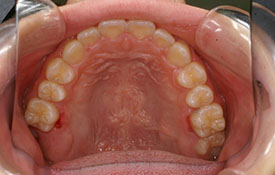

インビザラインの治療例:CASE-1

| プロフィール | 42歳 女性 |

| 所見 | 他院で行われた矯正歯科治療後の後戻りに悩まれて来院されました。 アイライナーの装着は、1日平均20時間ほどでした。 |